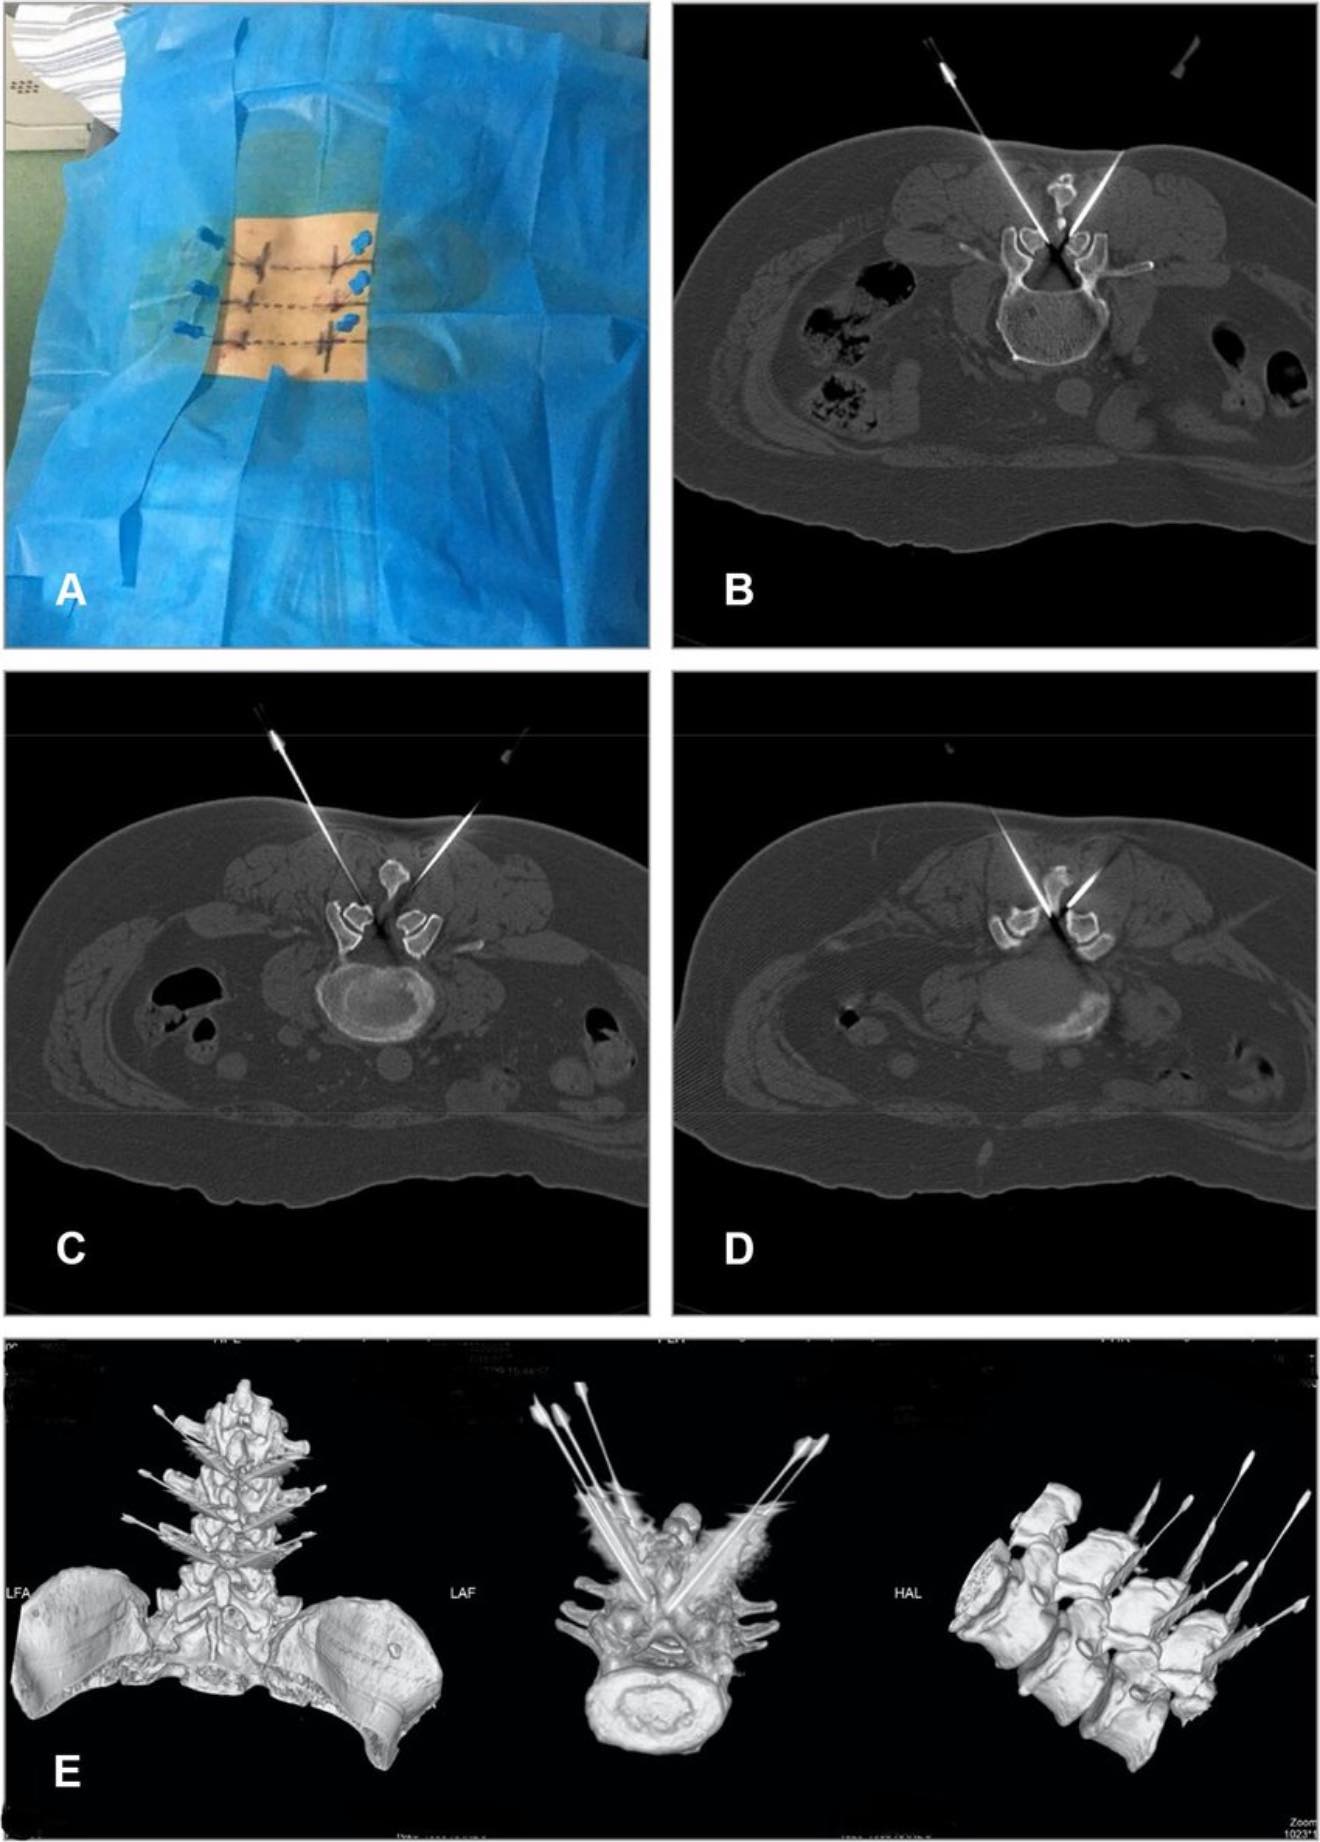

我沒有回答,而是讓數據來證明一切,我記錄每一位患者的影像變化,從黃韌帶 7mm 的壓迫,減少至 3-4mm,從VAS疼痛指數 8 分下降至 1 分,從無法行走到術後六週到八周內內回歸正常生活,這些結果讓所有的質疑聲都消失了,我成功了,我讓這項技術在台灣生根發芽,並且成為微創屠龍刀減壓治療的標準之一

當年,我在屍體解剖室裡親手解剖過無數脊椎,我在黃韌帶的夾縫中尋找那條最安全的通路,如今,我站在台灣最頂級的私人脊椎微創減壓針刀診所,為患者施行這項技術,當他們從手術台上站起來,當他們流著淚對我說「徐醫生,謝謝你」,我知道,這一切的努力沒有白費⋯⋯⋯⋯